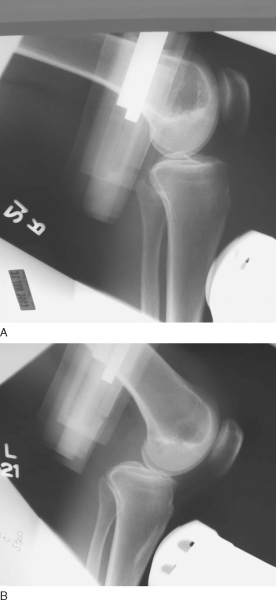

Injuries to the posterior cruciate ligament (PCL) are much rarer than those to the anterior cruciate ligament (ACL). Knowledge of and experience in evaluation and management of the PCL still lag behind those of the ACL. Recently, more emphasis has been placed on accurate evaluation and treatment of PCL injuries, either in isolation or in combined ligament injury patterns. The PCL serves as the primary restraint to posterior tibial translation at 90 degrees. Classically, the posterior drawer examination has been the standard for evaluation of PCL stability (

Fig. 68-1

). More recently, emphasis has been placed on objective measurement of posterior tibial subluxation (

Fig. 68-2

). [10] [11] Other components of the physical examination include the reverse pivot shift, quadriceps sag, quadriceps active test, and dial test. As always, comparison with the contralateral extremity should be performed. Radiologic evaluation should include anteroposterior and lateral radiographs and magnetic resonance imaging of the knee.